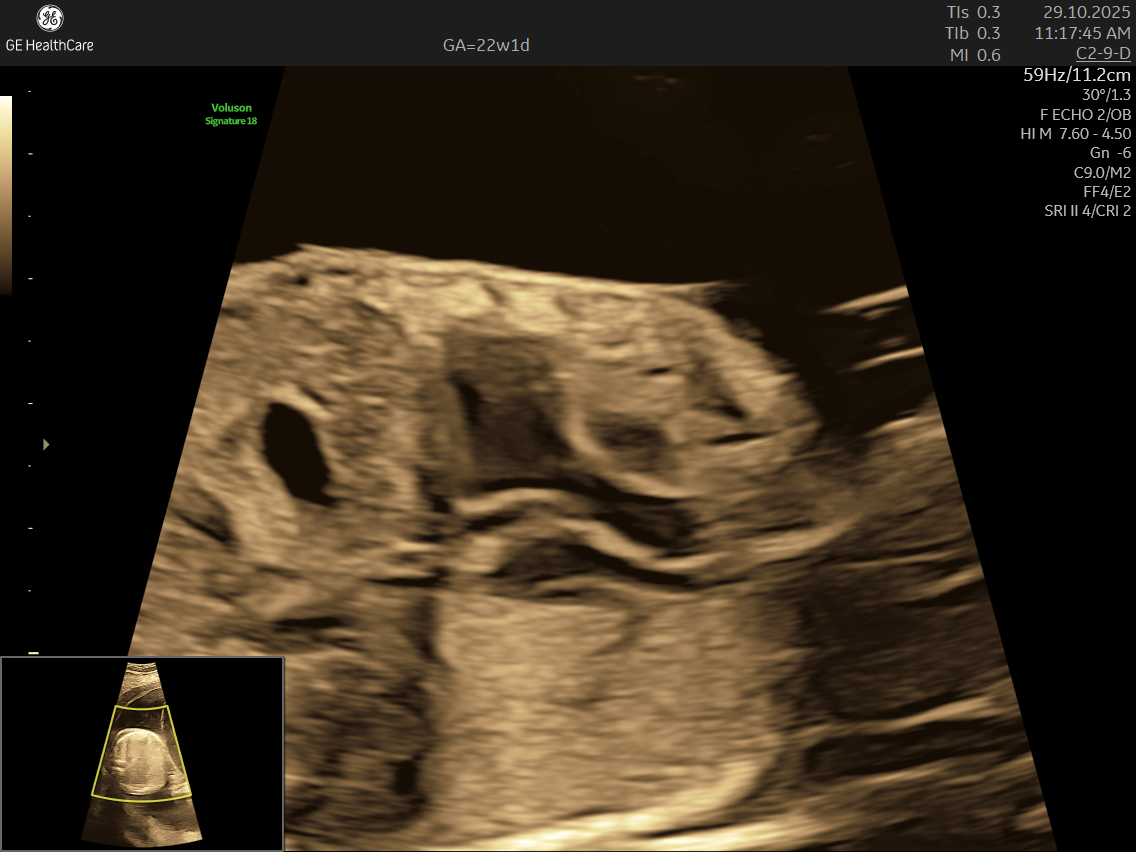

Fetal echocardiography is a valuabe early screening tool for Fetal Heart Defects. It is a specialized ultrasound scan that closely examines your baby’s heart while still in the womb. Unlike standard pregnancy scans, this test focuses on evaluating the structure, function, and rhythm of the fetal heart—providing incredibly detailed insights that help detect and diagnose congenital heart defects (CHDs) and other abnormalities early.

- Specialized Equipment and Expertise: Performed with high-resolution machines and by specialist doctors, fetal echocardiography pinpoints tiny structural or functional abnormalities that conventional scans may miss—helping ensure early, accurate diagnosis and informed planning.

- Using the advanced GE Voluson S10 ultrasound machine—renowned for its superior imaging clarity, 4D real-time visualization, and automated analysis tools that significantly increase diagnostic accuracy and reduce the chances of missing subtle heart defects.

- Its a specialized ultrasound done between 18–24 weeks of Gestational Age that evaluates the structure, function, and rhythm of a baby’s heart while still in the womb. This scan uses high-frequency sound waves to create detailed images of the fetal heart, aiding in the detection of congenital heart defects (CHDs) and other abnormalities.